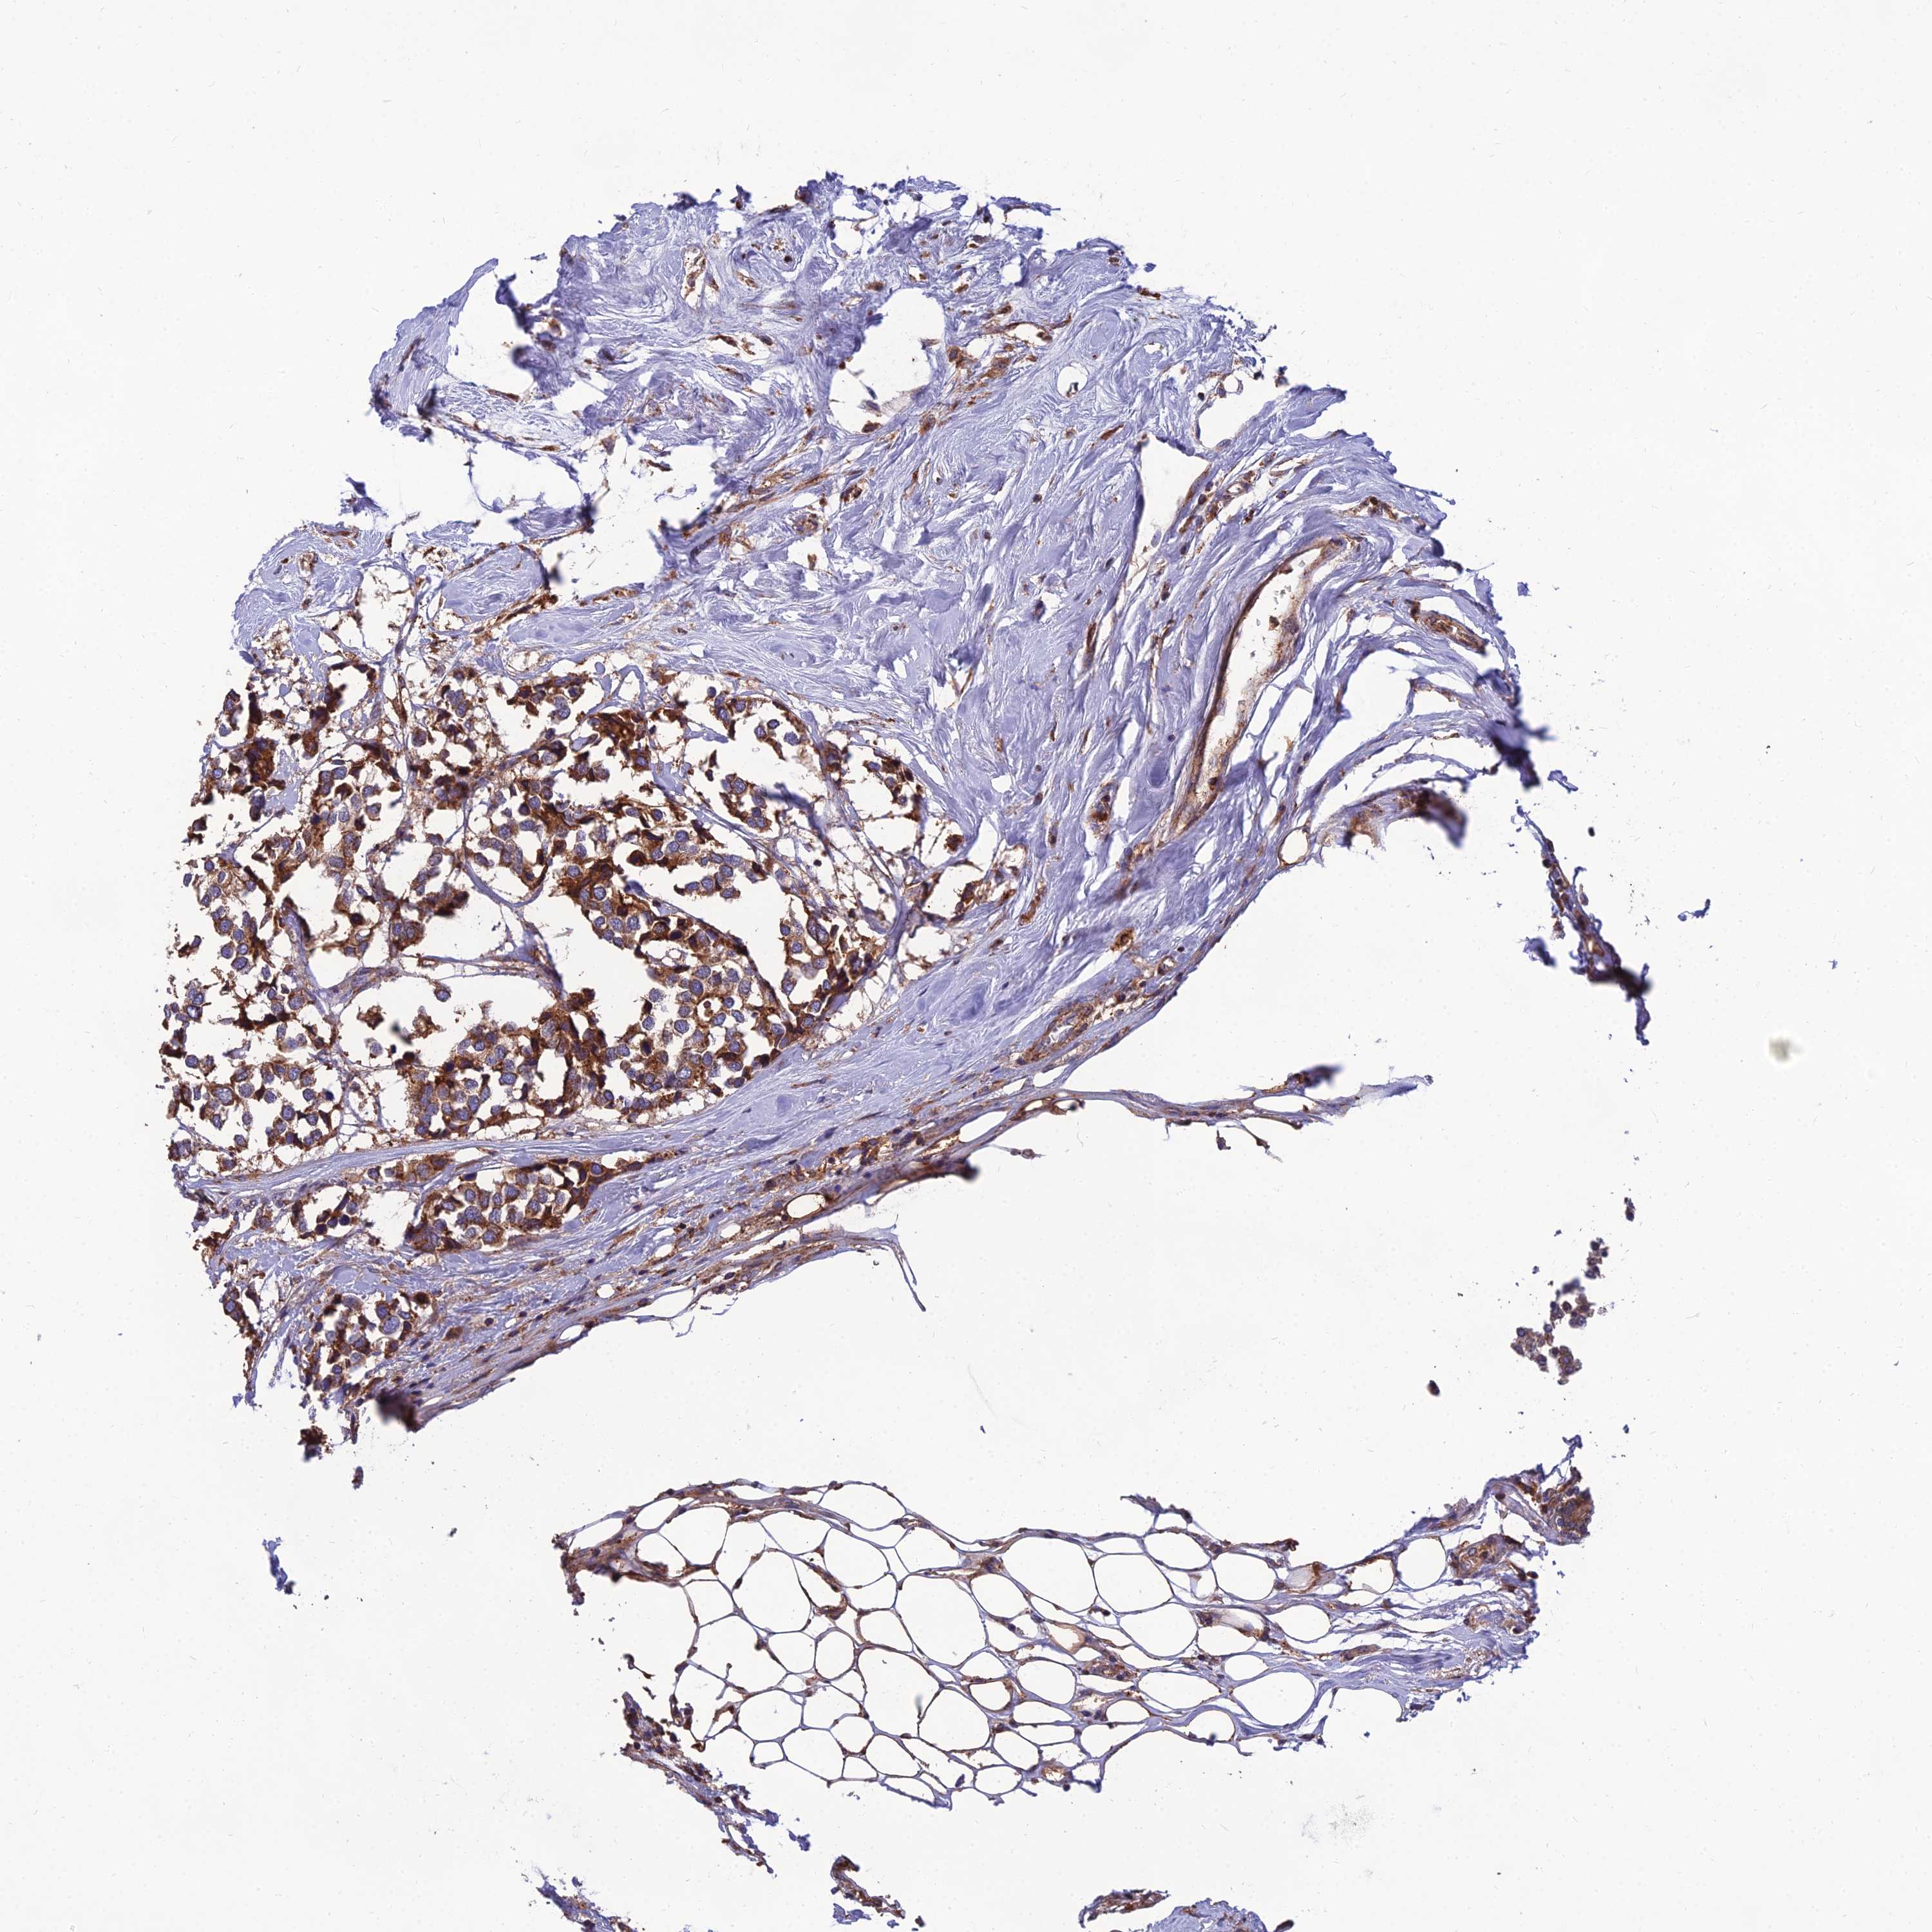

BRCA TCGA BRCA VALIDATION PROTEIN EXPRESSION

ANTIBODIES

AND

VALIDATION